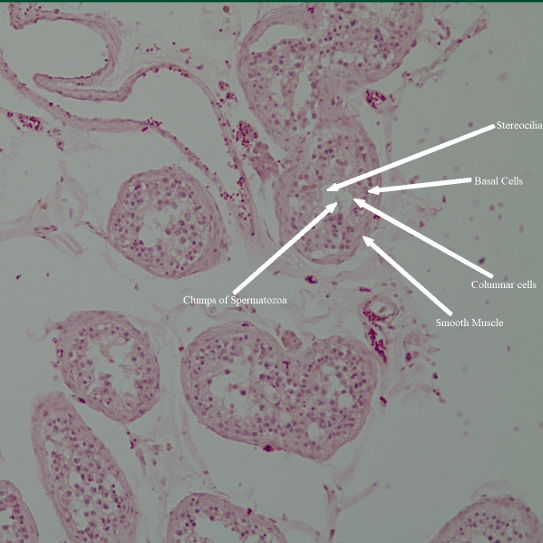

• In this course, I studied the structure, function, kinetics, and metabolic pathways of the biological macromolecules, and applied concepts of organic chemistry and biology. In lab, I learned to separate, detect, and modify biomolecules and used bioinformatic and computational techniques to assess this. The final project studied α-chymotrypsin catalysis of 4-nitrophenyl acetate in both pre-steady state and steady state using UV-vis. I learned to create a research article and analyze data using programs like Pymol, Desmos, KaleidaGraph, and KinTek Explorer.

• In this course, I studied the growth, identification, and function of pathogens, and the way the human body reacts to these pathogens. I learned aseptic techniques to isolate, culture, and identify different pathogens using staining and growth mediums.